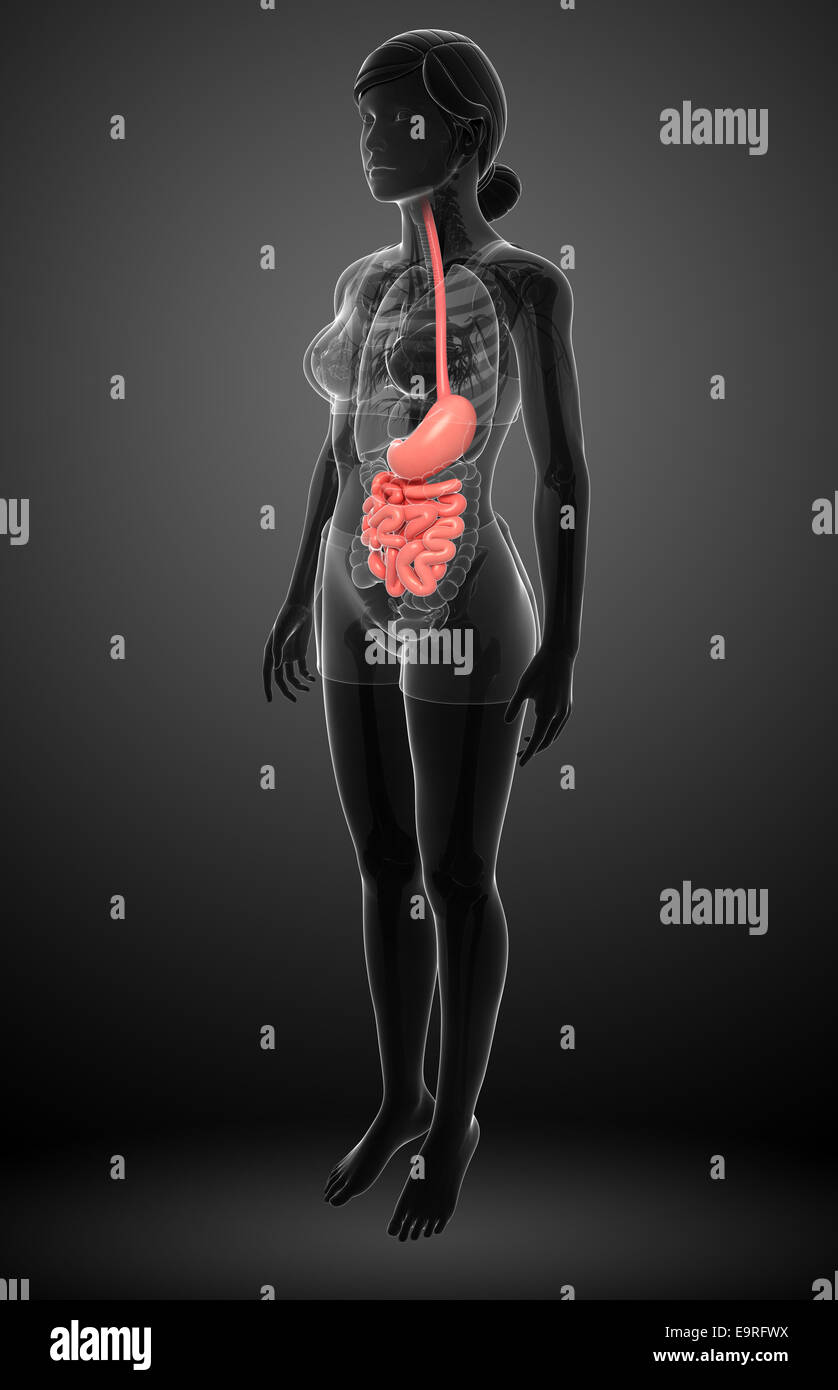

Illustration du petit intestin anatomie féminine Banque D'Imageshttps://www.alamyimages.fr/image-license-details/?v=1https://www.alamyimages.fr/photo-image-illustration-du-petit-intestin-anatomie-feminine-74890758.html

Illustration du petit intestin anatomie féminine Banque D'Imageshttps://www.alamyimages.fr/image-license-details/?v=1https://www.alamyimages.fr/photo-image-illustration-du-petit-intestin-anatomie-feminine-74890758.htmlRFE9RFWX–Illustration du petit intestin anatomie féminine